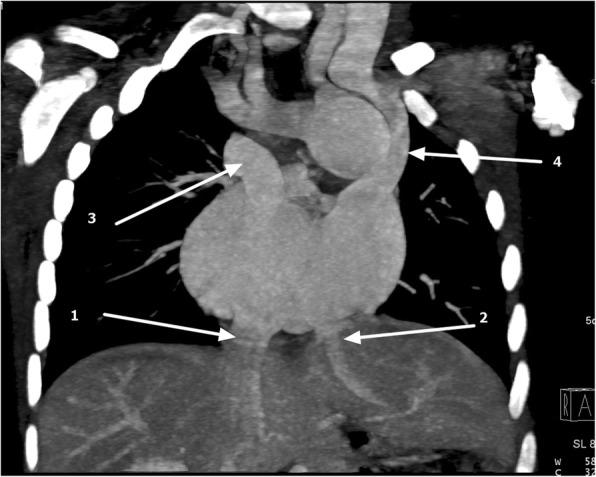

We report a case of a 31- month-old infant black girl in Tanzania who presented with an on-and-off history of difficulty in breathing, easy fatigability, facial and lower-limb swelling, recurrent respiratory tract infections, and failure to thrive.

我们报告了一名来自坦桑尼亚的31个月大黑人女婴的病例,该患儿有断断续续的呼吸困难、易疲劳、面部和下肢肿胀、反复呼吸道感染以及发育不良的病史。